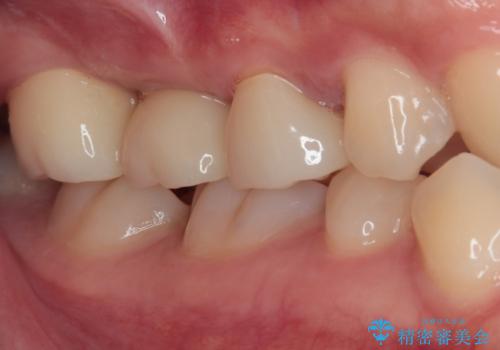

壊れやすいブリッジ インプラント治療で安定した咬み合わせに

- 頻繁に脱離を繰り返す奥歯のブリッジが欠けてしまったとのことで来院された患者様です。

外科処置を回避するためにブリッジ治療を選択されたそうですが、頻繁に脱離するので、欠けた部分のクラウンの作り替えと、欠損部のインプラント治療を行うこととしました。